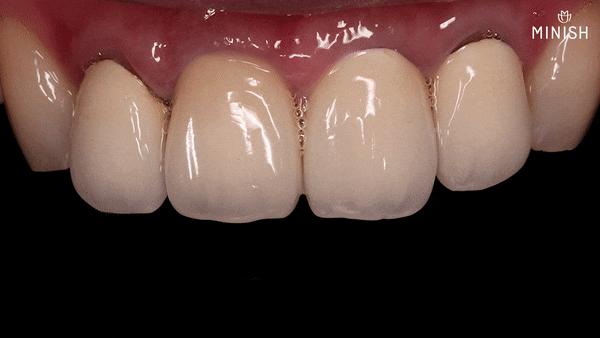

신경치료 이후 약해진 평택엄마의 앞니는 재치료를 통해 빈틈없이 코팅했습니다.

10여년 간의 치아복구 노하우로 얇으면서도 튼튼한 미니쉬 제작이 가능합니다.

얇은 두께 덕에 건강을 해치지 않으면서 자연스러운 형태와 색상을 나타냅니다. 보철물이 빈틈없이 결합되면 세균이 침입하지 못해 건강과 보철물 모두를 오래 사용할 수 있습니다.

돌출치아 개선 후

평생을 괴롭힌 못난 돌출치아, 하루만에 탈출 !

튀어나온 앞니를 교정치료나 무리한 삭제 없이 개선시켰다는 사실을 믿지 못하실 수도 있습니다. 거짓말 같을 정도로 빠른 기간 내에 효과적인 결과를 냈으며, 동시에 건강까지 회복시켰기 때문이죠.

최소한의 표면 청소만 필요한 MINISH! 신경치료 없이 돌출치아 콤플렉스를 해결합니다.

과한 삭제 없이도 비율을 조절해 대칭을 맞춤으로써 가지런한 배열을 만들 수 있습니다. 아름다운 평택엄마의 웃음, 돌출된 치아로 고민하던 과거는 기억나지 않습니다.